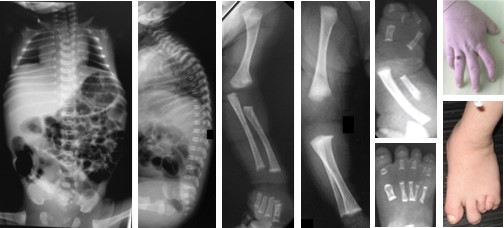

郭龙教授等在7个不相关家系中发现8位拥有类似表型的罕见病患者。通过外显子或基因组测序,发现患者均持有ERI1基因的双等位变异。这些患者中,拥有至少一个错义变异(missense variant)的患者表现出以“SEMD+指/趾畸形”为特征的严重骨骼发育异常(图2)。对比之下,仅含有无功能变异(null variant)的患者几乎没有指/趾以外的骨骼表型。这种错义变异较无功能变异引起更为严重表型的现象(表型二分类模型)在显性遗传病中较为常见,但在隐性遗传病中尚属首次报道。ERI1编码一种核糖核酸外切酶(exoribonuclease 1),调控小鼠多种RNA的代谢,其在人体中的作用尚不清楚。为了阐明ERI1变异引起的生物学效应,郭龙教授等利用患者来源的诱导多能干细胞(iPSC)等工具进行了一系列功能学研究,发现患者iPSC形成软骨类器官的能力下降,伴随5.8S核糖体RNA(rRNA)的成熟障碍以及细胞复制相关组蛋白信使RNA(mRNA)的降解缺陷(图3)。这些发现首次证实核糖核酸外切酶介导的RNA代谢过程对于人类软骨的发育和稳态维持至关重要,为软骨相关疾病治疗方法的开发提供新线索。

图2 郭-坎波型脊柱骨骺发育不良的骨骼表型(从左到右可见: 扁平椎、长管状骨的骨骺及干骺端发育不良、指/趾畸形)